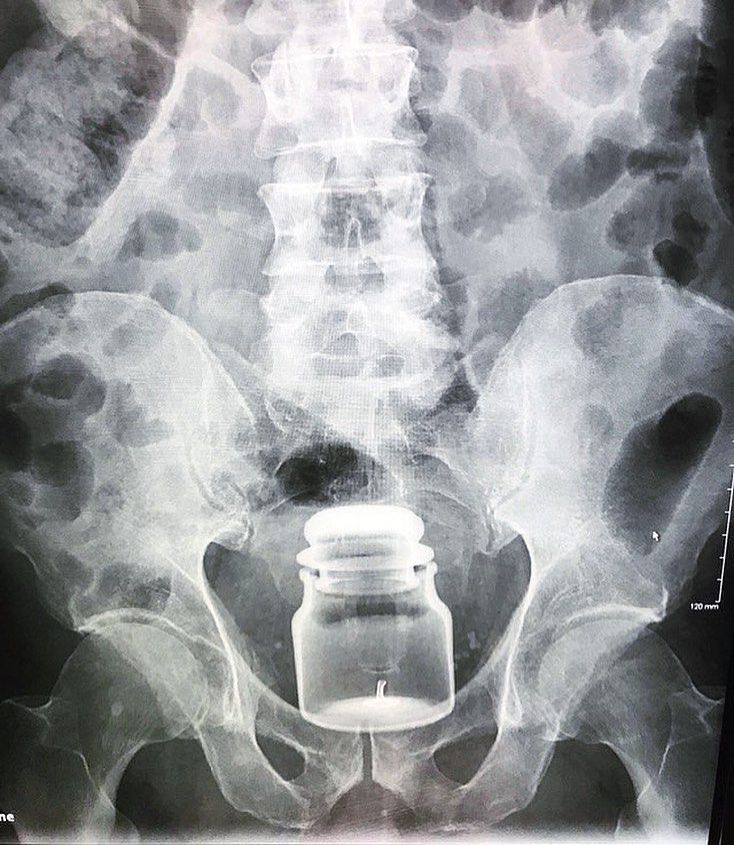

Rare case of foreign body - this patient came to the ER with a yankee candle lodged in his rectum!! Entrapped anorectal foreign bodies are being encountered more frequently in clinical practice. Many patient say they simply slipped and fell on the object. Majority of cases are the result of insertion during erotic activity. Most objects are introduced through anus; however, sometimes, a foreign body is swallowed, passes thruogh the gastrointestinal tract, and is held up in the rectum. Numerous objects, including billy clubs, various fruits and vegetables, light bulbs, bottle, Impulse body spray cans, and turkey basters have been described as retained rectal foreign bodies. There is a wide variety of objects and variation in trauma caused to local tissues of the rectum and distal colon. One of the most common problems encountered in the management of rectal foreign bodies is the delay in presentation, as many patients are embarrassed and reluctant to seek medical care. Most of these patients present to the emergency room after efforts to remove the object at home. Moreover, in the emergency room, patients may often be less than truthful regarding the reason for their visit, leading to extensive workups and further delays. Even after extraction, delayed perforation of or significant bleeding from the rectum may occur. Hence, a stepwise approach that includes diagnosis, removal and postextraction evaluation is essential. Typical clinical findings of a rectal foreign body are pain with defecation, abdominal pain, rectal bleeding, pruritus, and constipation. Delays in seeking medical attention and multiple attempts at self-removal can lead to mucosal edema and muscular spasms, making removal of the object more difficult. Diagnosis is confirmed by plain abdominal radiographs and rectal examination. Manual extraction without anaesthesia is only possible for very low-lying objects. Patients with high- lying foreign bodies generally require general anaesthesia to achieve complete relaxation of the anal sphincter to facilitate extraction. Open surgery should be reserved only for patients with perforation, peritonitis, or impaction of the foreign body. Photo by @dr.nirhus